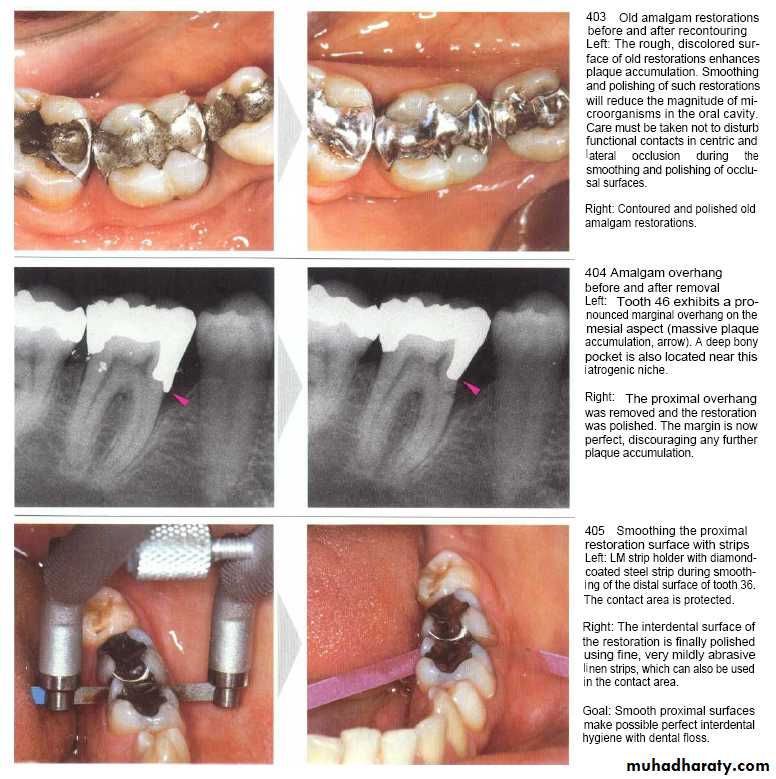

COLLEGE OF DENTISTRYRemoval of plaque retentive factors:

replacement.Using scaler or file.

Flame shaped diamond bur mounted on H.P. for rotating movement.

Flat diamond stone bur mounted on H.P. for horizontal reciprocal movement (EVA system).

Metal strip with special handle.